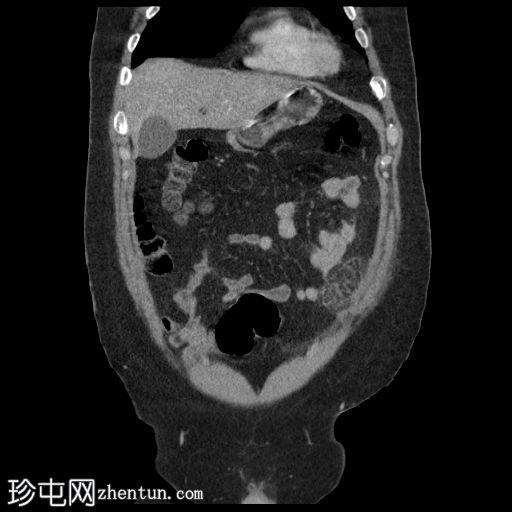

CT

冠状位增强扫描(门静脉期)

左髂前窝可见一卵圆形局灶性腹膜内脂肪条索影,周围环绕一薄层高密度环。

影像

表现符合大网膜梗死。

脂肪密度影大于3.5 cm提示大网膜梗死而非大网膜垂炎。然而,这两种情况均属于良性、自限性腹膜内局灶性脂肪梗死的范畴,无需手术干预。